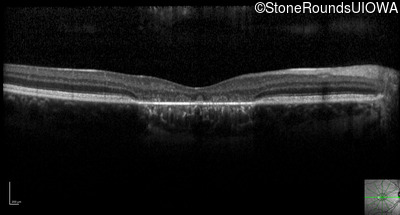

Optical Coherence Tomography - Left - 20/100 -2 sc

Exemplar / OCT Stack